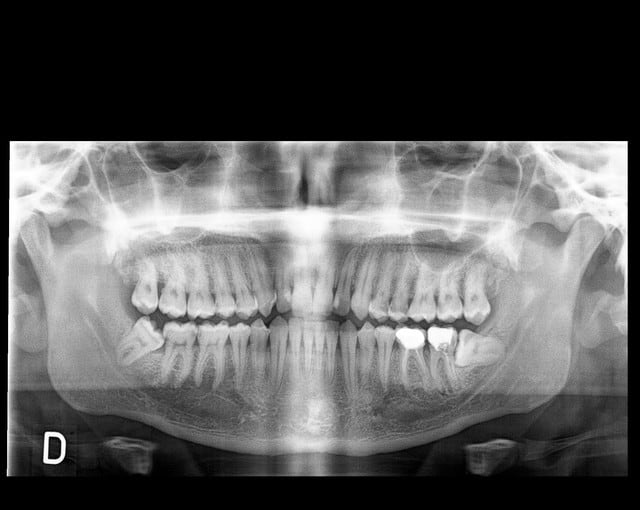

que feriez vous dans ce cas? extraire la 37 et tracter la 38 en position de la 37 ou preserver la 37 qui semble-t-il a un pronostic endodontique defavorable!

quel est le meilleur rapport benefice risque?

Perso:

Extrait 38 48 soins de toutes les caries et tenter sauver 37.

Si ça ne marche pas: implant.

Racines fines et longues et fragiles, risque de fracture, proximité du canal dentaire, racine de la 38 fermées, mauvaise position de la 38 qui va gêner la cicatrisation osseuse, et si complications -> obligation d'extraire la 38, mouvement othodontique très important dans un os néo formé pauvre, risque important de fonte de la racine 38, longueur d'un traitement qui donnera envie de l'arrêter.

Pour moi, très peu de chance de réussite.

Et grandes chances que quoique que tu fasses, cela se termine par un implant zone 37 à moyen ou long terme.